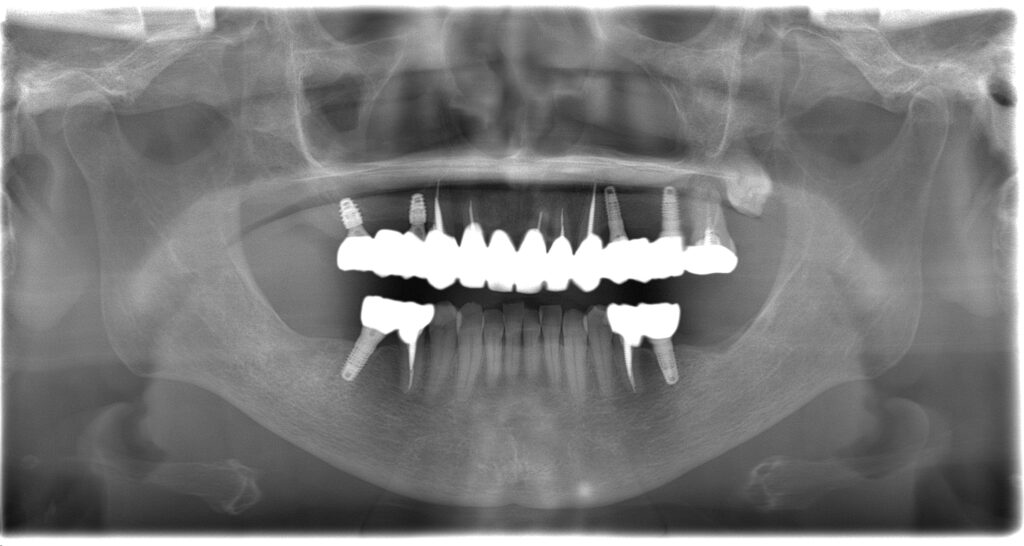

BEFORE

主訴

全体的に見た目を綺麗にしたい。奥歯でしっかり噛みたい。

診断名・主な症状

臼歯部欠損

年齢

70歳

治療内容

インプラント埋入(右上4・6,左上4・6,右下6,左下6)

ジルコニアBr(右上3―左上3)

ジルコニア(右下5,左下5)

治療期間/

通院回数

インプラント 1年5ヶ月/13回

ジルコニアBr、ジルコニアクラウン 3ヶ月/10回

費用

インプラント: 2,552,000円

その他治療: 640,000円

合計 3,192,000円

*いずれも税込